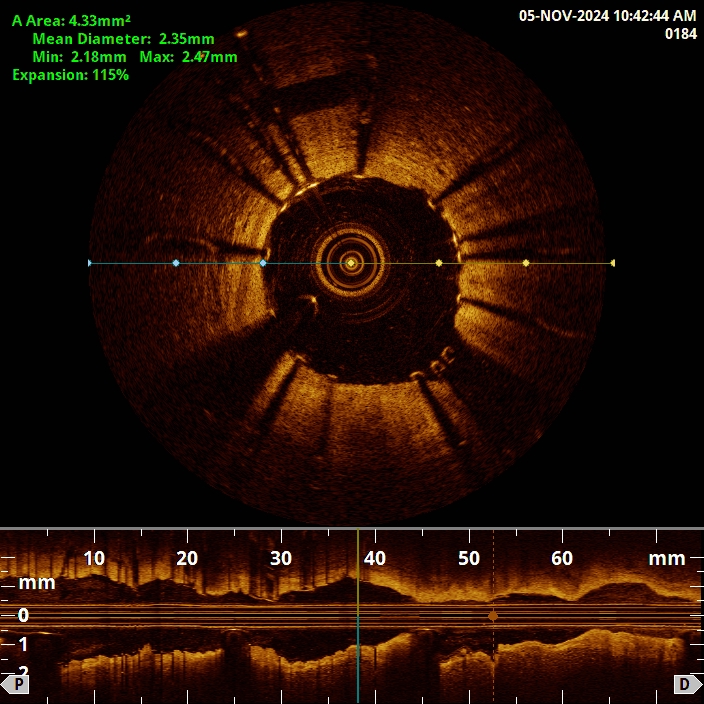

Die intravaskuläre Bildgebung ist eine moderne Erweiterung der Koronarangiographie mit der sich die Herzkranzgefäße hochauflösend von innen darstellen lassen. Während die klassische Angiographie lediglich das Gefäßlumen unter Verwendung von Kontrastmittel sichtbar macht, ermöglichen Verfahren wie die optische Kohärenztomographie (OCT) und der intravaskuläre Ultraschall (IVUS) eine detaillierte Analyse der Gefäßwandstruktur und der Beschaffenheit von Plaques.

- Die OCT arbeitet mit infrarotem Licht und liefert extrem hochauflösenden Bilder. Damit lassen sich feine Details wie dünne Plaquekappen, Mikrothromben oder Dissektionen präzise erkennen.

- Der IVUS nutzt hochfrequente Ultraschallwellen um Querschnittsbilder der Gefäßwand zu erzeugen. Die Auflösung ist etwas geringer als beim OCT dafür kann der IVUS auch in größeren Gefäßen sowie bei stärkerem Blutfluss zuverlässig eingesetzt werden. Er liefert wichtige Informationen über die Dicke der Gefäßwand, die Ausdehnung von Plaques und die exakte Gefäßgröße - Daten die für die Planung und Durchführung einer Koronarintervention entscheidend sind.

Beide Verfahren kommen bei uns am Standort regelmäßig zum Einsatz und helfen, Eingriffe gezielter und sicherer durchzuführen und die Langzeitergebnisse zu verbessern. Die intravaskuläre Bildgebung ist damit ein wertvolles Instrument in der interventionellen Kardiologie - besonders bei komplexen oder unklaren Befunden.

OCT Aufnahme zur Einschätzung der Stentapposition